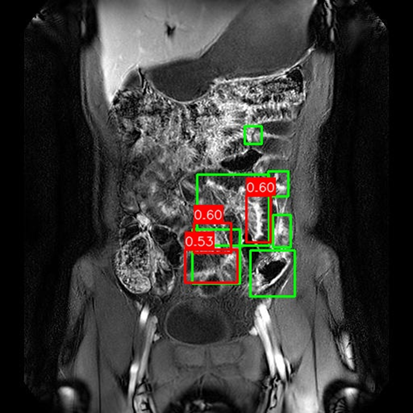

(a) Mask R-CNN [He2017MaskRCNN]

Refer to caption

(b) DiffusionDet [Chen2023DiffusionDet_ICCV]

(c) DeFloMat (Ours)

Figure 3: Qualitative Comparison on Crohn’s Disease MRE Test Set. The figure compares detection results from (a) Mask R-CNN, (b) DiffusionDet (S=3S=3), and (c) DeFloMat (Ours, S=3S=3) on challenging MRE slices. Green boxes indicate True Positives (TP, IoU 0.1\geq 0.1), Red boxes indicate False Positives (FP), and Purple boxes indicate False Negatives (FN). DeFloMat consistently demonstrates superior localization quality and sensitivity: it successfully detects subtle inflammation regions (TP) that are often missed (FN, Purple boxes) by the Mask R-CNN baseline (Row 2, 4). Furthermore, DeFloMat provides tighter bounding box localization compared to DiffusionDet, confirming the benefit of learning the direct, deterministic flow field. The results show DeFloMat’s robustness in capturing varying sizes and numbers of inflammatory lesions.

Qualitative Assessment.

Figure 3 provides visual evidence of the models’ performance on challenging MRE slices, where inflammatory lesions can be subtle or obscured. The qualitative results underscore DeFloMat’s enhanced localization fidelity. In challenging cases (e.g., Row 2 and 4), Mask R-CNN and DiffusionDet frequently produce False Negatives (FN, Purple boxes), failing to detect clear inflammation sites. In contrast, DeFloMat reliably converts these FNs into True Positives (TP, Green boxes) by providing tighter and more accurate bounding box predictions. This suggests that the deterministic velocity field learned via Flow Matching is highly effective at precisely directing the proposal centers towards the true lesion locations, a characteristic that is vital for accurate clinical reporting. DeFloMat’s ability to achieve such precise localization with only S=3S=3 steps highlights its clinical utility for rapid diagnostic auxiliary systems.